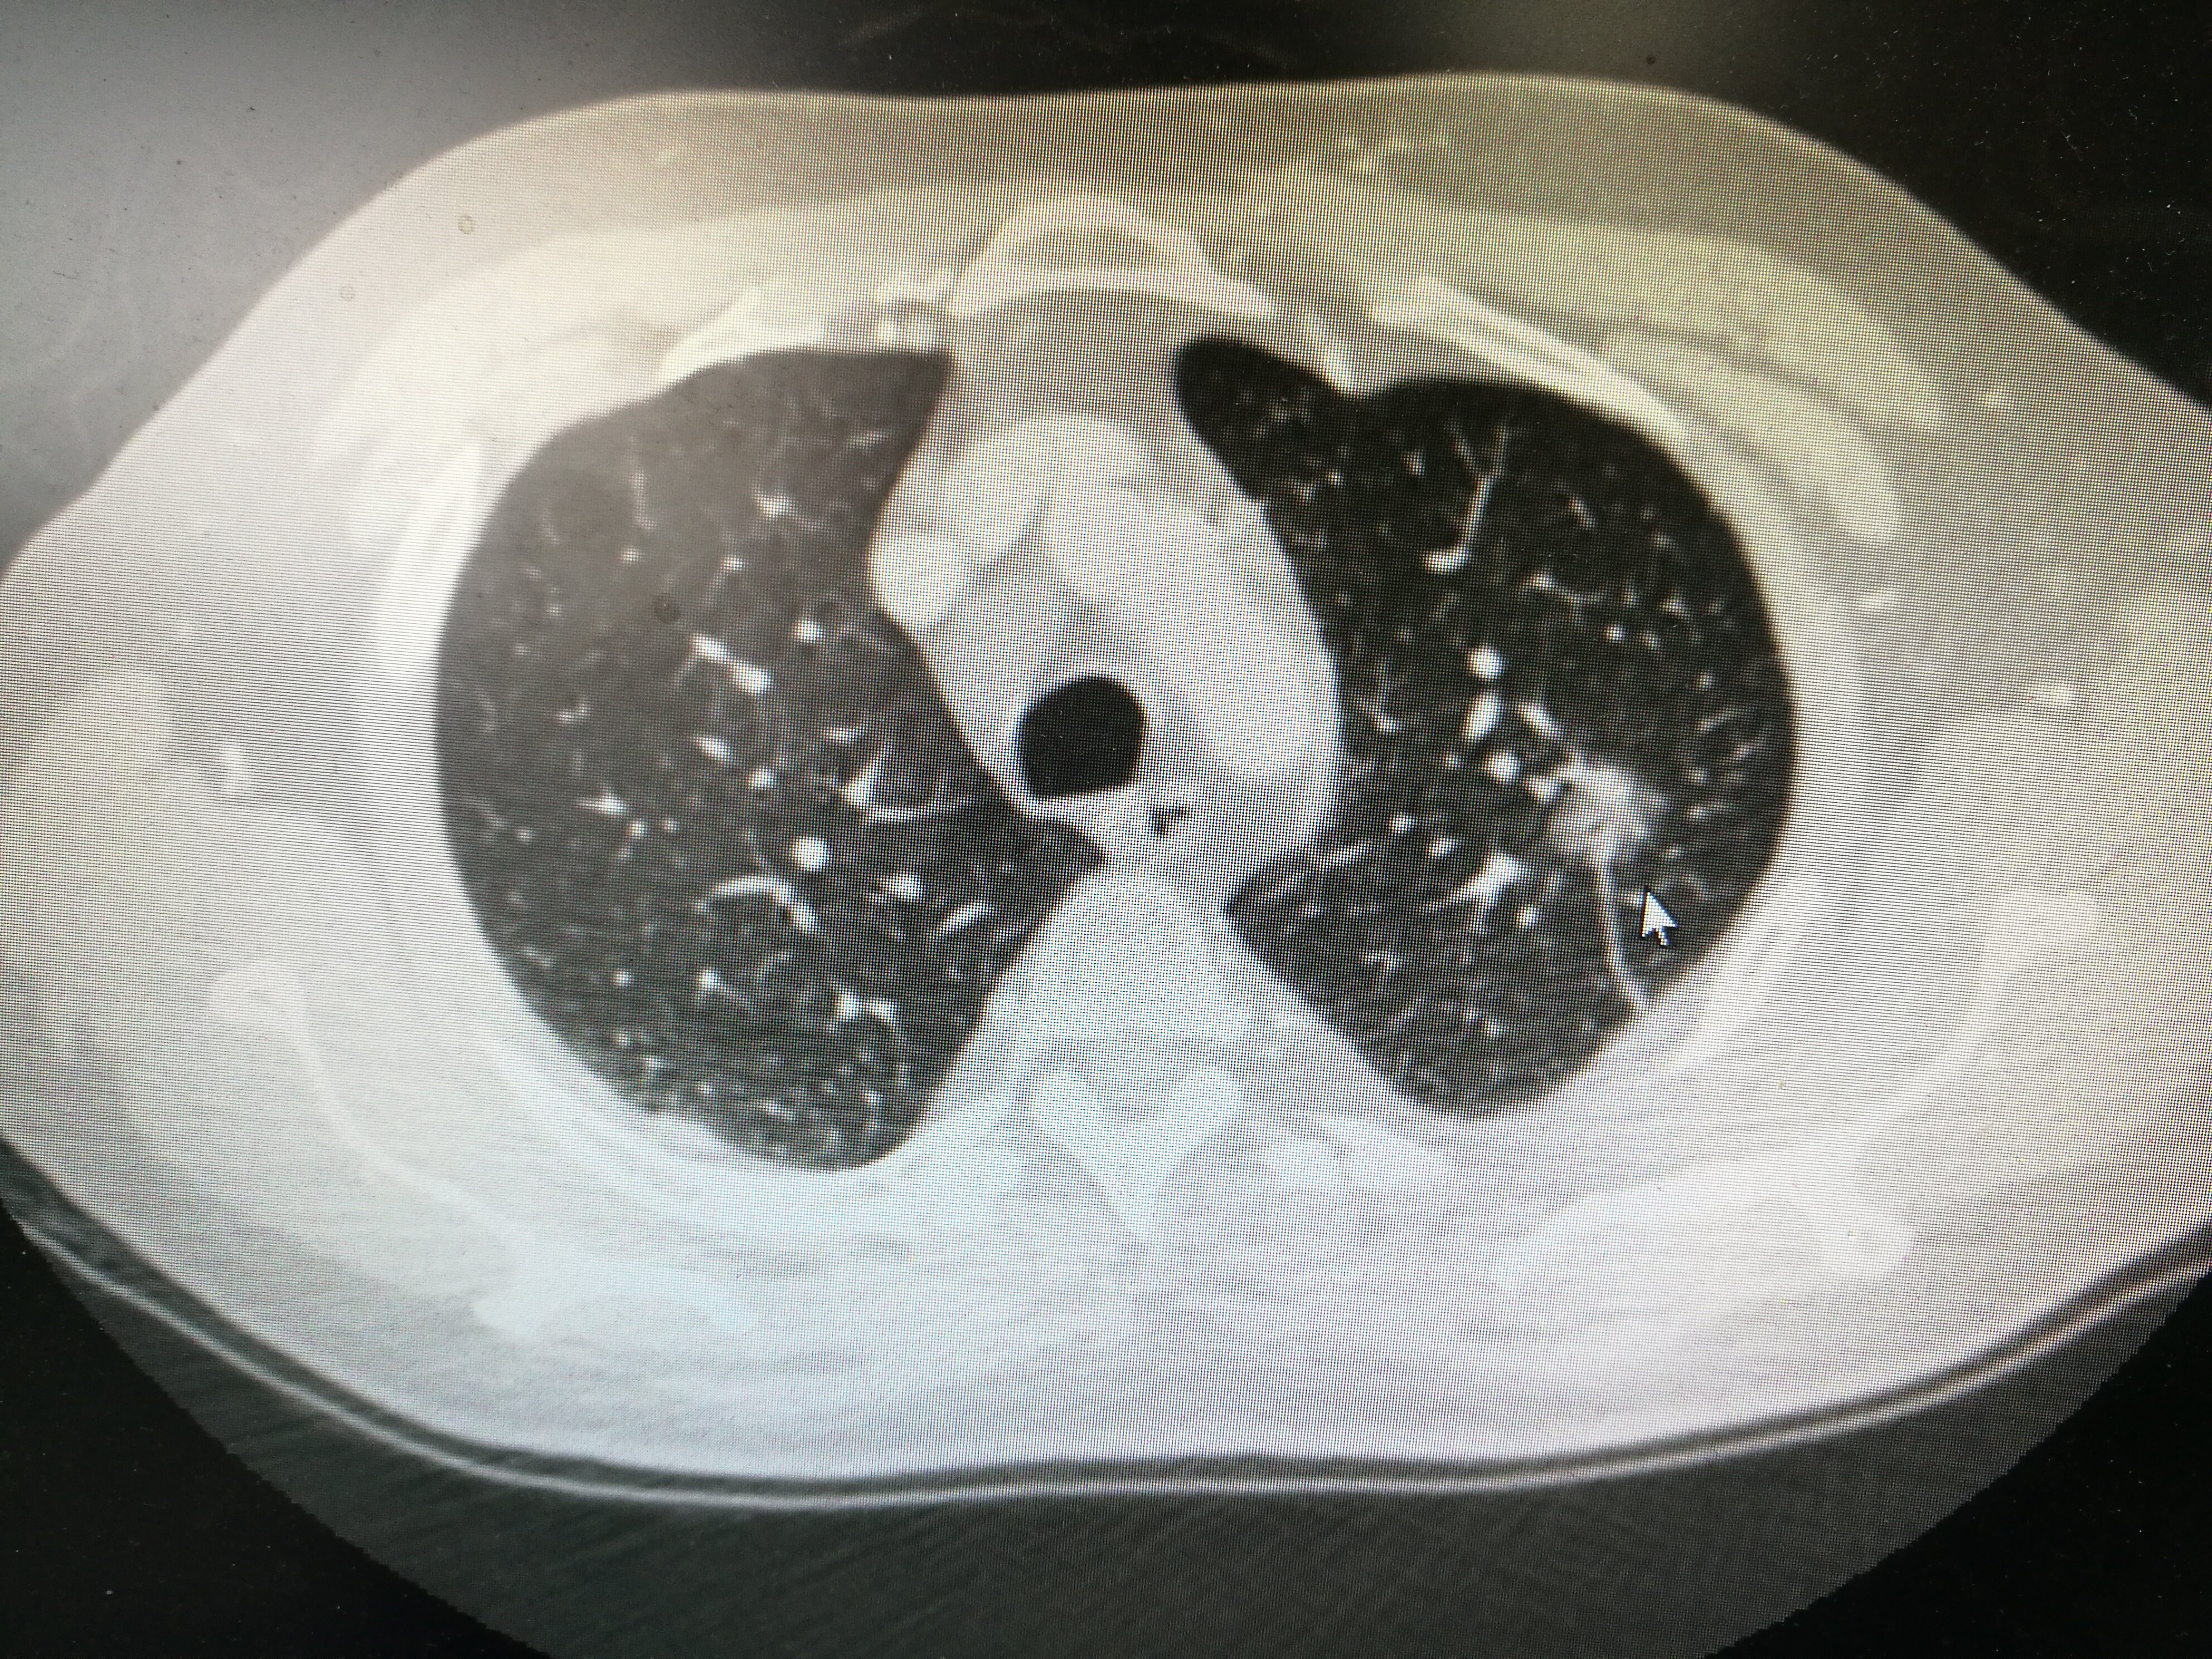

许多人在体检中意外发现肺部结节时,常常感到困惑和担忧:“我为什么没有咳嗽、胸痛等症状,却发现了肺部结节?”、“肺部结节是不是就意味着我得了肺癌?”

随着CT技术的普及和人们对健康检查的重视,肺结节的发现率正在逐渐增加。据统计,大约95%的肺结节是良性的,这 means 大多数肺结节并不会引起明显的症状。